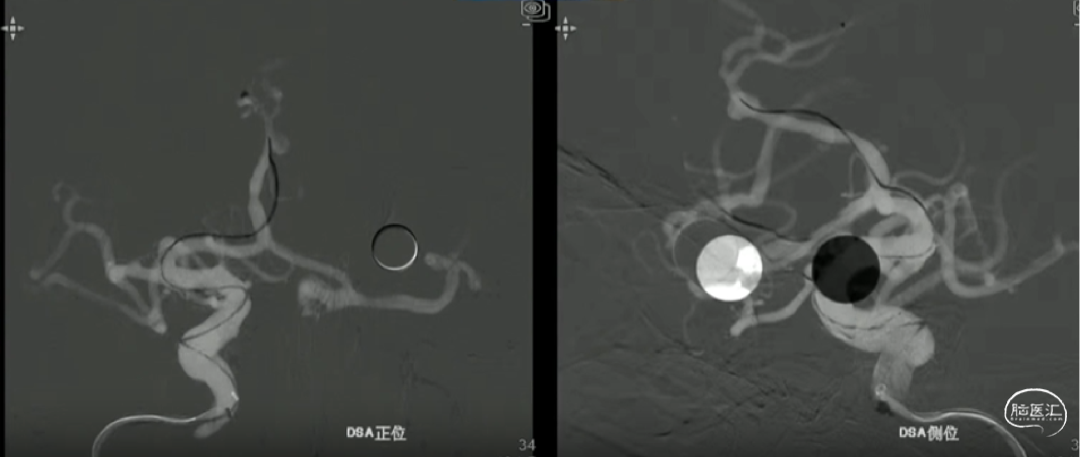

如意输送到位

心玮“如意”FDD-250-20mm 血流导向密网支架输送到位。

如意远端释放

动脉瘤近端锐角弯曲,颅内支撑导管位置较低,且血管迂曲,无法提供很好的支撑和力的传导,故支架推送中阻力较大,需双手操作,给予支架推送杆一定张力。